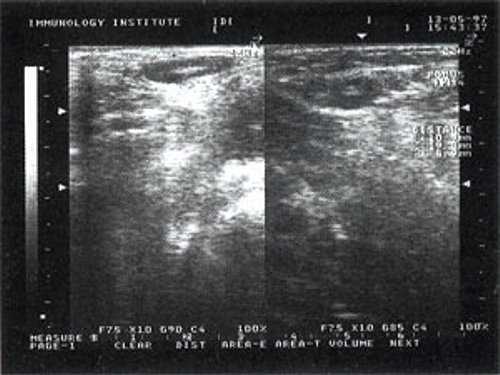

При повторных УЗ осмотрах на фоне массированной противовоспатительной терапии было отмечено увеличение числа лимфатических узлов вовлеченных в процесс активизации. При этом заметной перестройки эхоструктуры и уменьшения размеров в наблюдаемых лимфатических узлах отмечено не было (рис 4).

Рис. 4. Варианты изображения увеличенного лимфатического узла с УЗ-признаками доброкачественной аденопатии у больного с синдромом иммунодефицита.

Мы выявили совершенно другую УЗ-картину состояния пальпируемых лимфатических узлов при динамической оценке у больных с синдромом иммунодефицита. Оцениваемые лимфатические узлы имели эхографические признаки доброкачественного процесса, в большинстве наблюдений их размеры превышали 2-2,5 см. При этом во всех случаях дифференцировались составные части лимфатического узла. Определялся узкий кортикальный слой и широкая гиперэхогенная сердцевина при сохранении овальной конфигурации и соотношении поперечного/переднезаднего более 1.